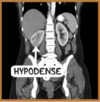

Hallazgos tomográficos en pielonefritis aguda

- Zonas hipodensas